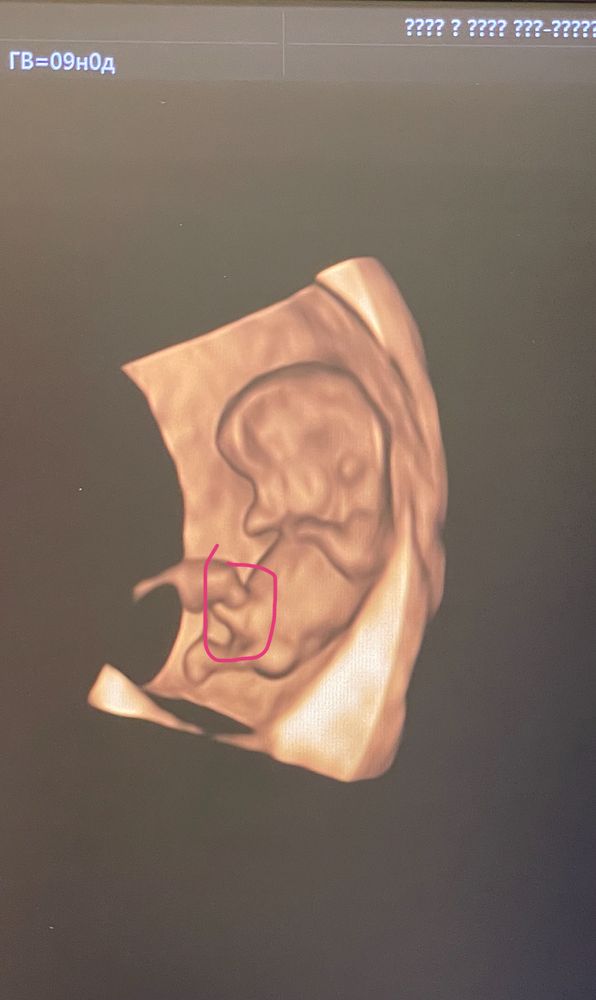

M, мне в 9 недель сказали точно))))) Изображение

10.07.2024

Best mammy , Это 4Д УЗИ?

Планяша, вроде да